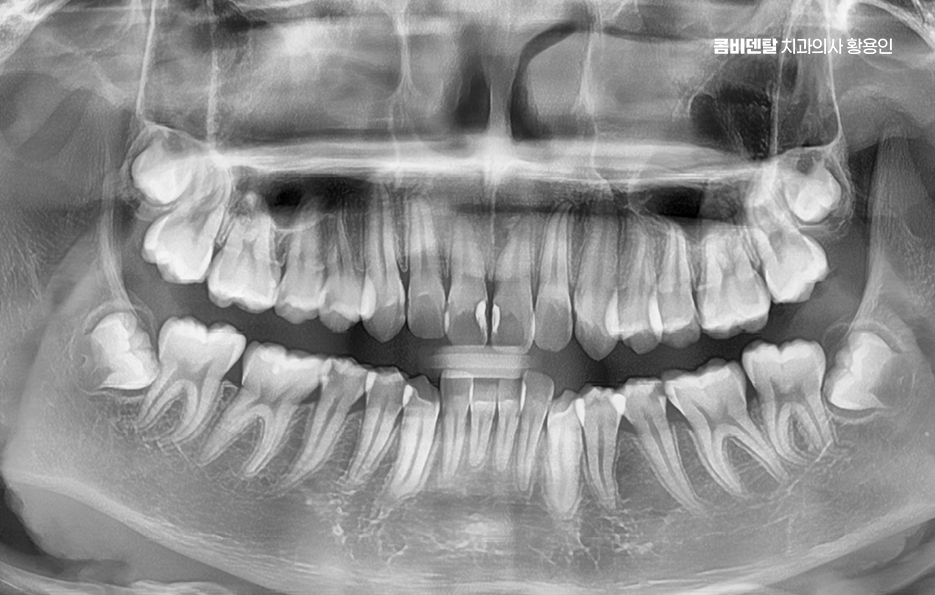

그렇다면 이런 부정교합 문제를 해결하기 위해선 어떤 방식으로 치료계획을 세워야 하느냐가 중요한데 첫 번째 단계는 정밀한 진단과 분석으로 단순히 눈으로 보기엔 어느정도 가지런해 보여도 실제로는 턱의 중심선이 틀어져 있거나, 치아의 경사가 비정상적으로 되어 있을 수 있기 때문에 파노라마 X-ray, 세팔로, 구강 스캐너, 3D CT 등을 통해 턱의 구조, 치아 배열, 뼈 상태 등을 면밀히 분석해야 정확한 치료계획이 세워지는 거예요.